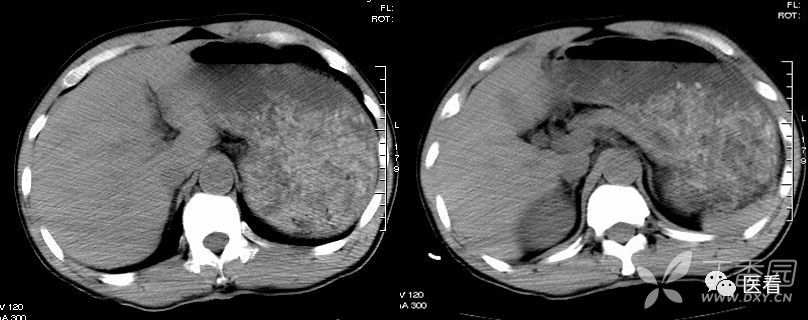

6 团注高浓度碘对比剂(红箭头)形成的伪影(白箭头)

注入造影剂的方法有快速静脉滴注法和静脉团注法(bolus injection)。静脉滴注法以20ml ~30ml/min速率滴注造影剂,待开始扫描时,造影剂已分布于动脉期、静脉期和平衡期,不能进行分期扫描,现已基本不再使用。目前主要采用静脉团注法中的动态团注CT增强扫描(Dynamic bolus contrast-enhanced scan)。动态团注CT增强扫描又称动态CT增强扫描(Dynamic enhancement CT scan),是一种对注射造影剂速度、扫描时间进行程序控制的增强CT检查技术。检查前根据需要预先设定扫描层面、扫描次数、间隔时间和床动速度等参数;使用高压注射器,短时间内快速将造影剂团注(bolus)入静脉。注射速率一般为2~3ml/s,根据需要,注射速率可增至5ml/s,目前文献报告最大注射速率为10ml/s。造影剂总量80~180ml。

对于团注高密度碘对比剂,可以采用足端→头端扫描而规避。